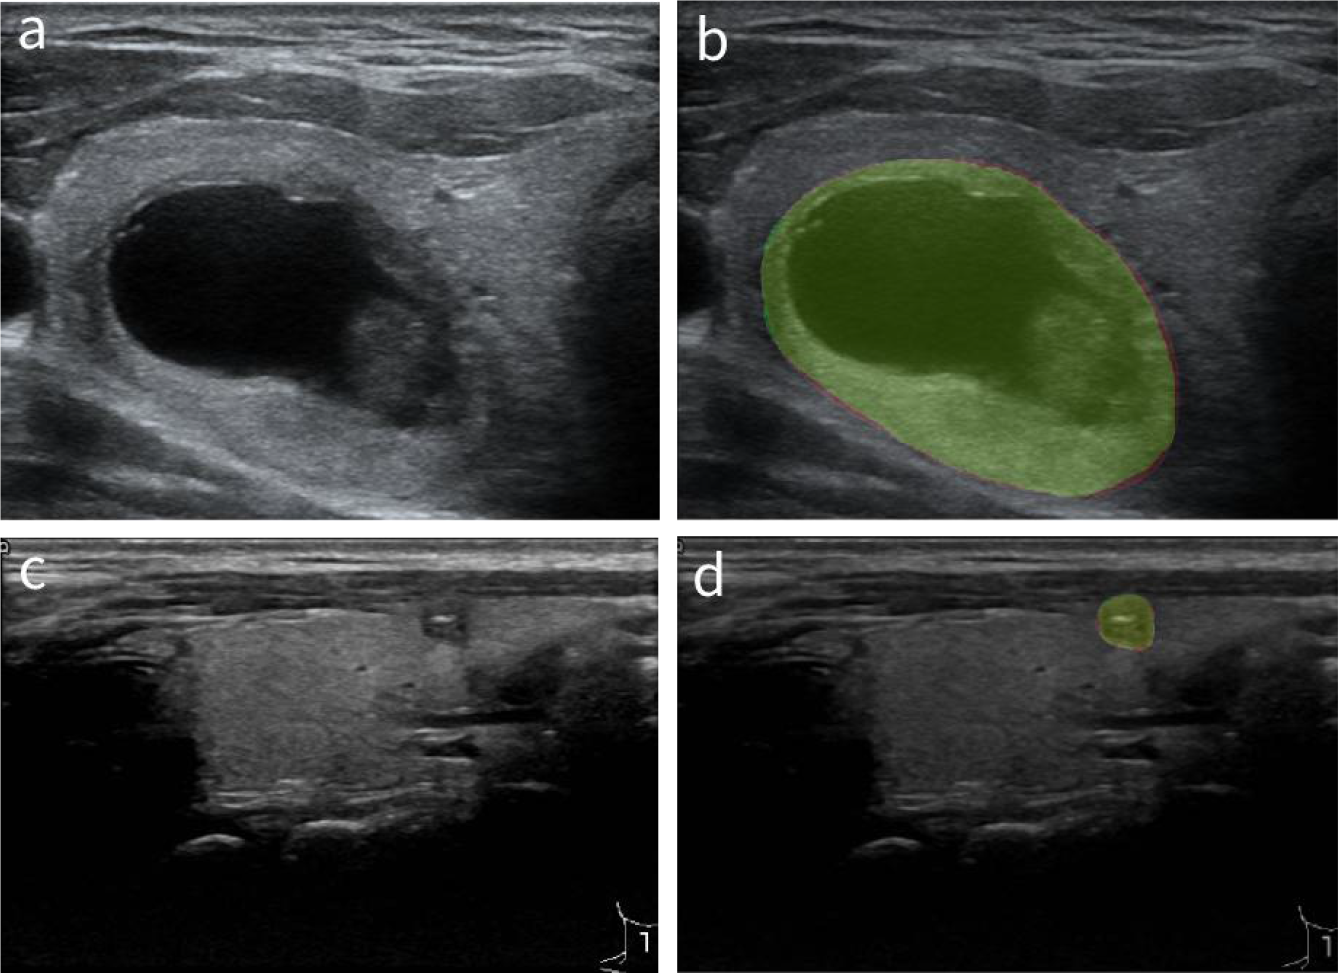

In order to verify the pathological significance of the heat maps, we first compared the nodule masks generated by the AI system with the masks outlined by the radiologists of different nodule sizes in Figure 6 to show that the basis for computing the heat maps is pathologically relevant. We calculated the dice similarity coefficient (Dice) as a metric to evaluate how well the AI system performs for localizing thyroid nodules within the gland tissues, with the result shown by the boxplot in Figure 7. It can be found that the masks outputted by the AI system are highly overlapped with the masks delineated by the radiologists (the median dice coefficient >0.9), demonstrating the high accuracy of the AI system in identifying the nodule areas. This verifies that the area of the heat map is mainly in the lesion area, as nodule segmentation is a key step for heat map computations.

Figure 6

Comparison of the masks generated by the AI system and the masks outlined by the radiologists. (A, C) The original thyroid ultrasound images. (B, D) Masks generated by the AI system and radiologists, where the red segments are produced by the AI system, and the green ones are manually drawn by the radiologists. AI, artificial intelligence.